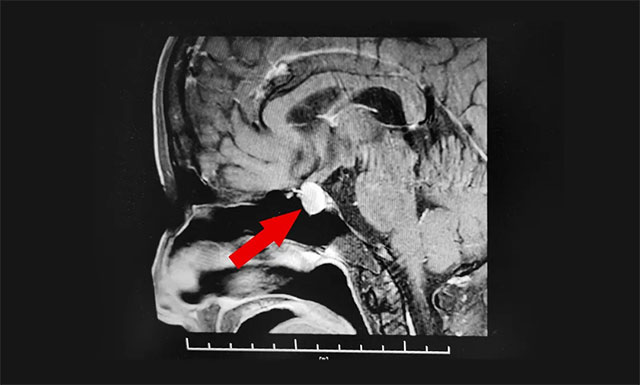

经检查,患者双眼视力下降。针对患者情况,6B病区主任潘仁龙基于多年临床经验立即作出判断,急行头颅鞍区MRI平扫+增强,显示:垂体窝可见类椭圆形异常信号,病灶大小约1.3.*1.2*cm,垂体柄未见显示,视交叉轻度上抬。“多一分钟和少一分钟,对患者的预后可能就不一样。这种情况必须立即明确病情并进行手术治疗。”潘仁龙主任表示,“患者一个多月前就出现头痛、视力急剧下降,到达医院时已经耽误了很长时间,所以我们的救治必须争分夺秒。”

▲ 术前MR影像:垂体大腺瘤,超蝶鞍生长

核磁共振检查结果很快出来了:考虑垂体大腺瘤伴卒中。“一般来说,垂体瘤压迫引起的头痛和视力减退不会那么来势汹汹。但患者因为垂体瘤内出血,导致垂体瘤体积在瞬间增大数倍,压迫鞍隔出现剧烈头痛、呕吐等脑膜刺激症状,再向上压迫视神经造成视力、视野的改变,甚至会永久失明,最终会导致下丘脑受损,出现昏迷直至离世,后果不堪设想。”潘仁龙主任表示。